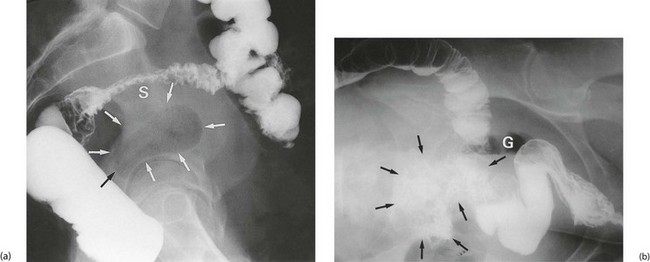

The consequences of diverticular inflammation are collectively described as diverticulitis and are summarised in Figure 29.3. Most people with diverticula are asymptomatic, and diverticula are a common incidental finding when the colon is investigated by barium enema or colonoscopy. Typical appearances are shown in Figures 29.2 and Fig. 29.4.

Fig. 29.2 Diverticular disease

Barium enema showing the typical appearance of multiple diverticula (arrowed) in the sigmoid and descending colon in a 77-year-old woman. A few diverticula are also present in the transverse colon